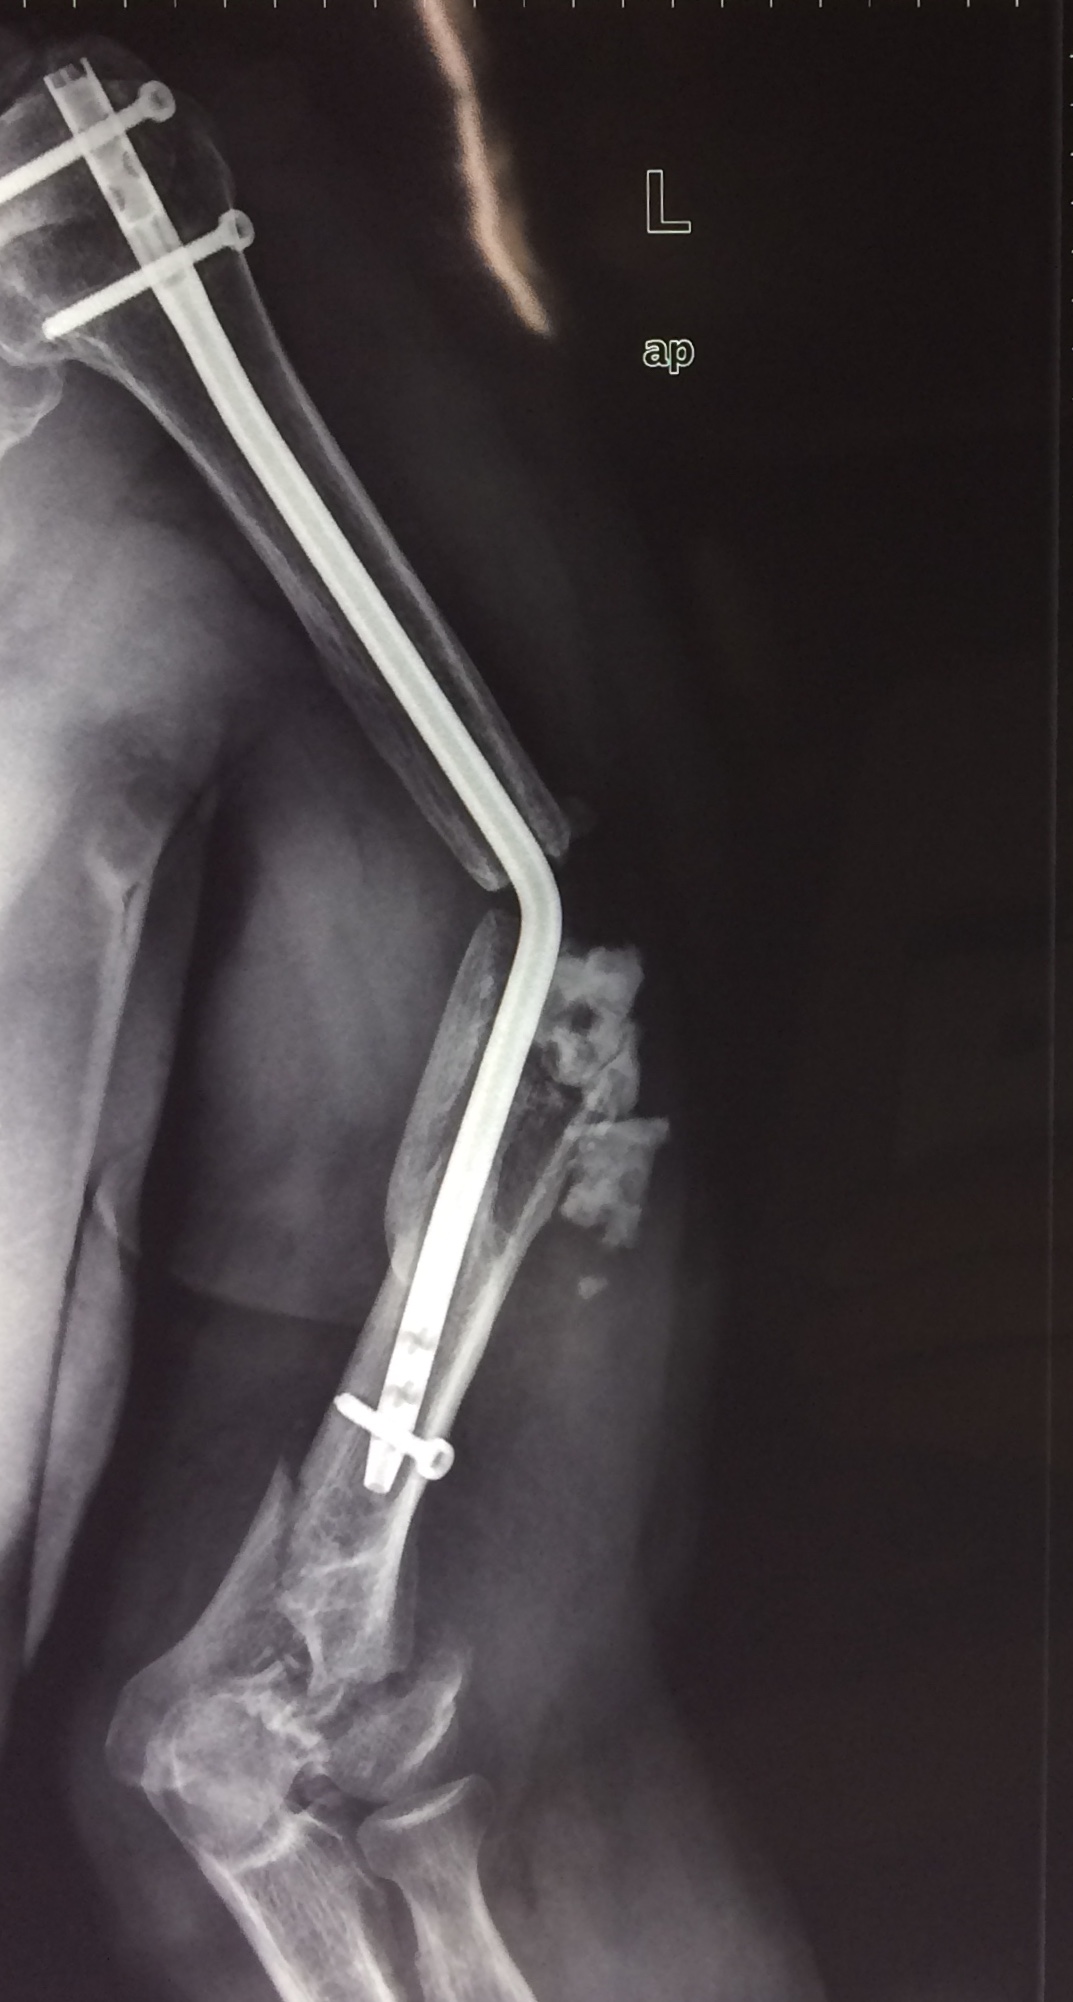

п·я┤п╣п╫я▄ п╫я┐п╤п╣п╫ я│п╬п╡п╣я┌ п╨п╬п╩п╩п╣пЁ, п╨я┌п╬ п╡я│я┌я─п╣я┤п╟п╩ п©п╬п╢п╬п╠п╫я▀п╣ я│п╩я┐я┤п╟п╦.

п п╟п╨ я┐п╢п╟п╩я▐я┌я▄ пЁп╡п╬п╥п╢я▄, п©п╬п╫п╟п╢п╬п╠я▐я┌я│я▐ п╨п╬я│я┌п╫я▀п╣ я┌я─п╟п╫я│п©п╩п╟п╫я┌п╟я┌я▀, п©п╬п╡я┌п╬я─п╫п╟я▐ я└п╦п╨я│п╟я├п╦я▐ -

п÷п╩п╟я│я┌п╦п╫п╟ п╦п╩п╦ пЁп╡п╬п╥п╢я▄?